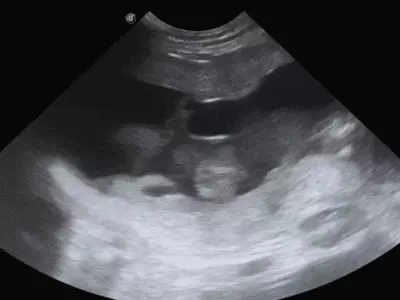

W tym wydaniu m.in: problemy trawienne, dermatozy psychogenne psów, przepuklina brzuszna pępkowa zewnętrzna, szpiczak mnogi, starszy pies z objawami krwioplucia, przegląd objawów behawioralnych w kontekście różnych chorób.